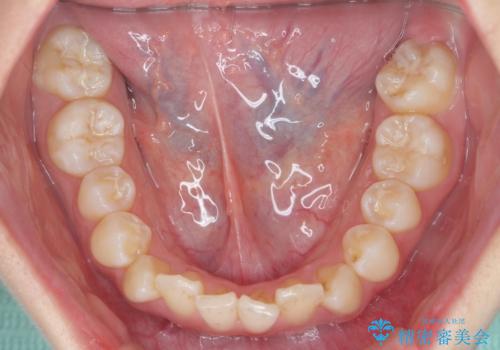

インビザラインライトで行う短期マウスピース矯正治療

- 前歯のガタつきを並べたいたいと、矯正治療を希望され来院されました。

とにかく短期間で前歯だけの治療を行いという希望が強く、全体矯正と前歯だけの部分矯正の仕上がりのイメージを確認したのち14枚のマウスピースで前歯のみの矯正治療を行っていくこととしました。

インビザラインライトは軽度なガタつきや傾斜の改善に用いられる全14枚のマウスピース矯正です。

短期間で治療の終了が見込めるだけでなく、料金もインビザラインフルに比べリーズナブルです。